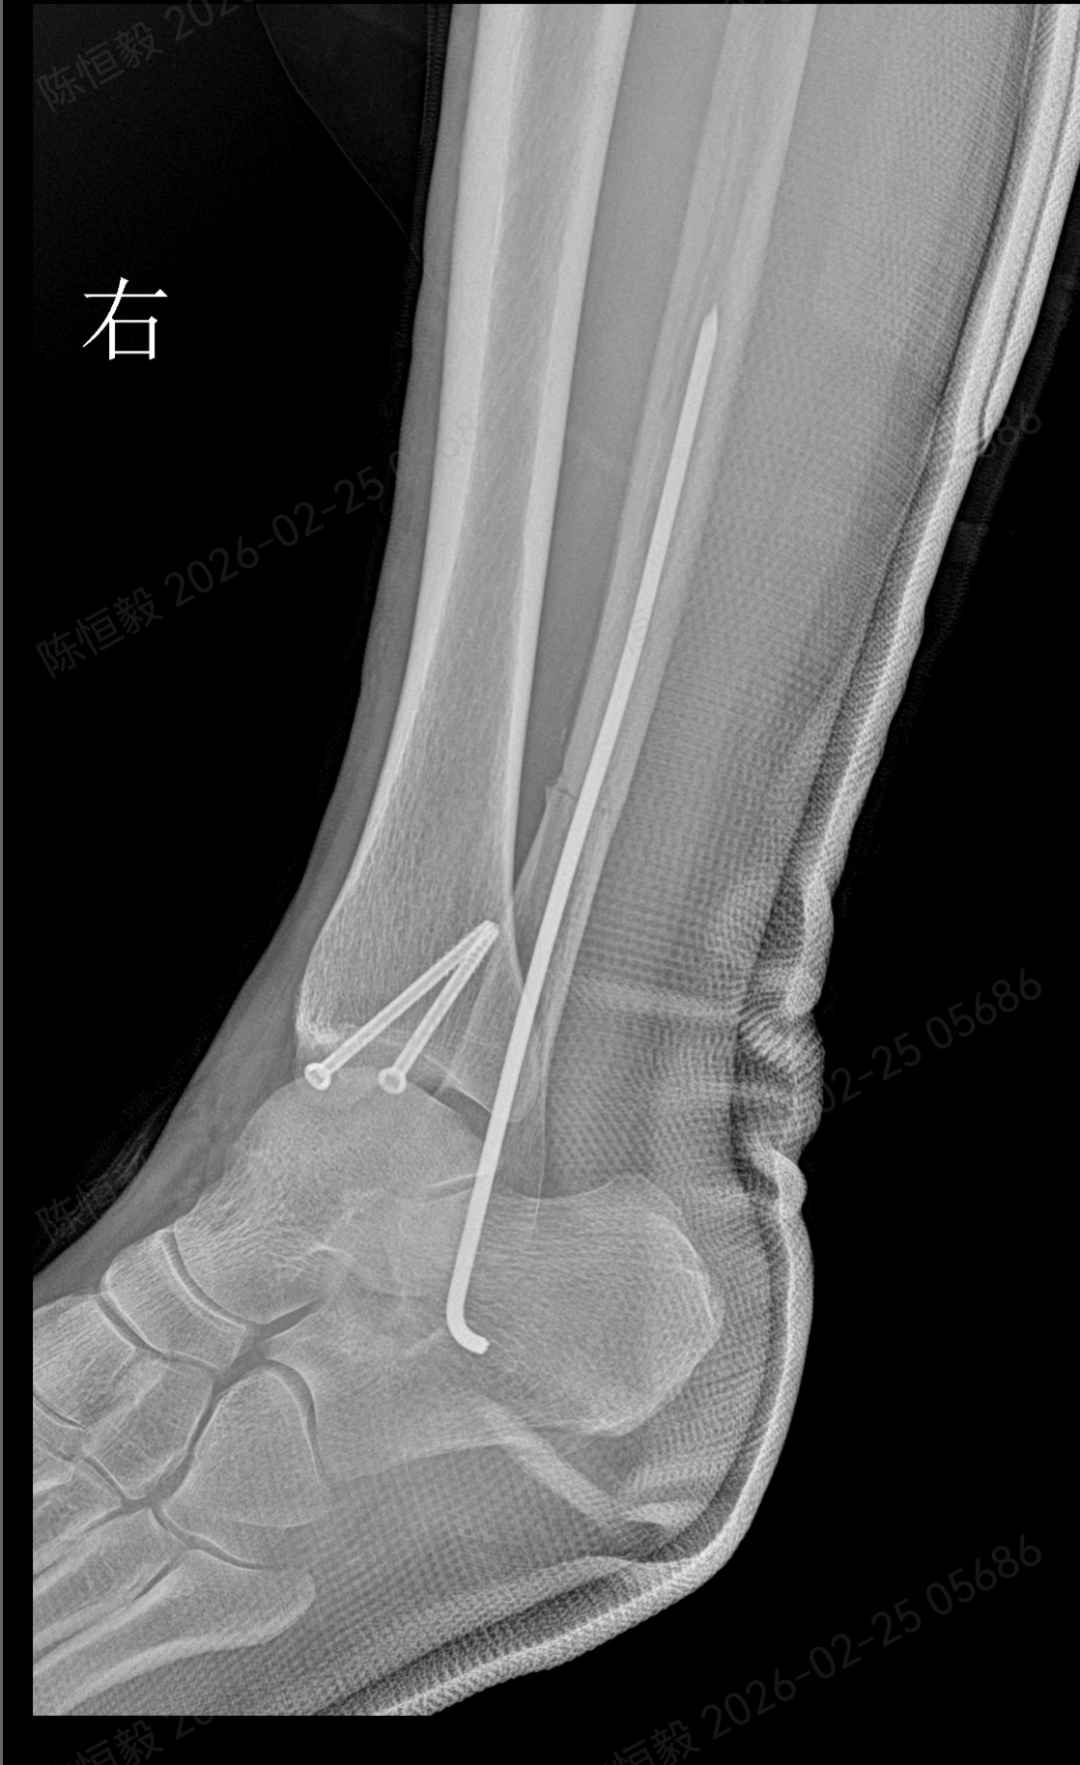

针对王女士的踝关节骨折情况,由副主任医师陈涛主刀,足踝外科团队为其实施了关节镜辅助下机器人导航微创闭合复位内固定术。

通过 5 毫米小切口将关节镜探入关节腔内,清理腔内淤血与致炎因子,清晰观察骨折块移位及关节软骨损伤情况;

在关节镜直视下,使用微创器械将骨折块复位至解剖位置,恢复关节面平整;

依托机器人导航系统,规划螺钉置入通道,避开关节面与重要组织;

最后通过另外两个 5 毫米的小孔置入空心螺钉,完成骨折端的稳定固定。

整个手术仅通过三个 5 毫米的小切口完成,最大程度降低了手术创伤。

术后第二天,王女士便可在床上进行踝泵训练;

术后第三天,在充气靴保护下能够部分负重行走;

术后两周复查,手术切口愈合状况良好,几乎无明显痕迹。